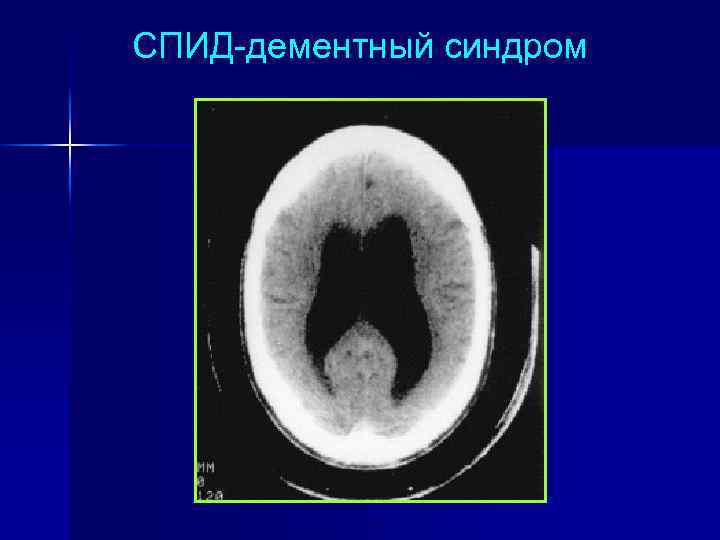

СПИД-дементный синдром